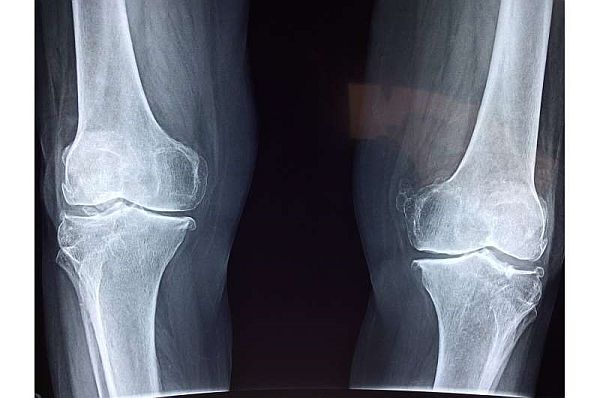

Protein giúp ngăn chặn quá trình thoái hóa sụn khớp gối

Theo các nhà khoa học, hiện chưa có cách chữa khỏi bệnh viêm xương khớp, nhưng các nhà khoa ở Hoa Kỳ đã sử dụng phương pháp tiêm ở đầu gối giúp ngăn chặn tác động của bệnh. Họ cho thấy mục tiêu cụ thể ở protein qua chuột, đưa nó vào trạng thái quá tải và ngăn chặn quá trình thoái hóa sụn theo thời gian. Dựa trên phát hiện đó, việc điều trị cho chuột bị thoái hóa sụn đầu gối do phẫu thuật thông qua kỹ thuật nanomedicine hiện đại làm giảm đáng kể tình trạng thoái hóa sụn và đau đầu gối.

Giáo sư Ling Qin, cho biết: "Phòng thí nghiệm của chúng tôi là một trong số ít trên thế giới nghiên cứu về tín hiệu của thụ thể yếu tố tăng trưởng biểu bì (EGFR) trong sụn, chúng tôi đã phát hiện ra rằng, sự thiếu hụt hoặc bất hoạt EGFR làm tăng tốc độ tiến triển thoái hóa khớp ở chuột. Do đó, sự kích hoạt của nó có thể được sử dụng để điều trị viêm xương khớp và trong nghiên cứu này, lần đầu tiên chúng tôi đã chứng minh được khi kích hoạt quá mức EGFR bên trong đầu gối sẽ ngăn chặn sự tiến triển của viêm xương khớp”.

Những thử nghiệm từ các phòng thí nghiệm khác hoạt động với EGFR đã cho kết quả "khó hiểu và gây tranh cãi". Nhưng phòng thí nghiệm của Ling Qin đã tìm ra mối liên hệ giữa viêm xương khớp và thiếu hụt EGFR, điều này tạo nên nền tảng cho giả thuyết của họ.

Các nhà nghiên cứu đã so sánh những con chuột điển hình với chuột có phân tử liên kết với EGFR, được gọi là phối tử, có biểu hiện quá mức trong tế bào chondrocytes, các khối tạo ra sụn. Sự biểu hiện quá mức này dẫn đến việc kích hoạt mạnh tín hiệu EGFR trong sụn đầu gối.

Khi kiểm tra chúng, chuột có HBEGF biểu hiện quá mức (phối tử EGFR) được phát hiện thường xuyên có sụn mở rộng, có nghĩa là nó không bị mòn đi như những con chuột có hoạt động EGFR bình thường. Hơn nữa, khi những con chuột này ở độ tuổi trưởng thành, sụn của chúng có khả năng chống lại sự thoái hóa và nhiều dấu hiệu khác của viêm xương khớp, ngay cả khi sụn chêm của chúng bị hư hỏng.